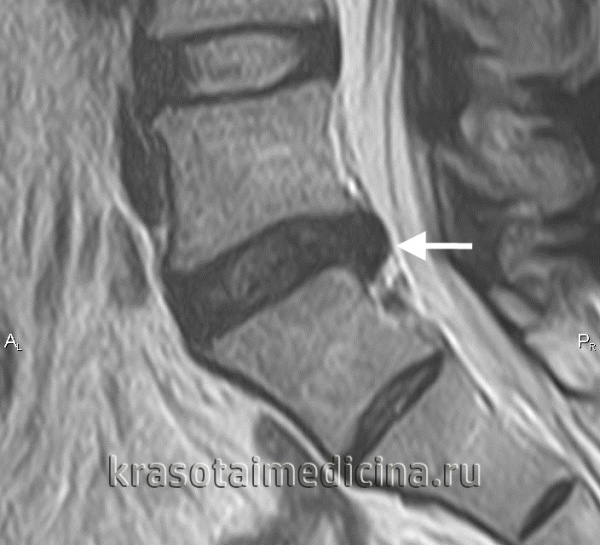

МРТ ШОП. Грыжевые выпячивания дисков в с. С5-С6, С6-С7 кзади, с выраженным сужением позвоночного канала и сдавлением спинного мозга

МРТ шейного отдела позвоночника. Межпозвонковая грыжа в сегменте С5-С6, отслаивающая заднюю продольную связку